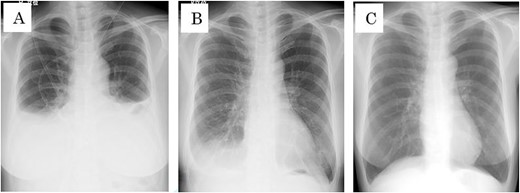

The patient was started on a diet the first day after surgery. On the third day postoperative, she complained of respiratory distress in a supine position, and cough reflex was observed during deep inhalation. Chest X-rays and CT showed pleural effusion in both lower lung fields (Fig. 3), and chylothorax was suspected based on the intraoperative and postoperative clinical findings. Approximately 600 mL of yellowish-white pleural fluid was aspirated during bilateral thoracic puncture. Furthermore, no swelling of the neck was observed, and the contents of the neck drain were serous and had a concentration of 15 mg/dL of triglyceride, which was within the normal range. Therefore, no evidence of chyle leakage was observed in the neck. On the other hand, the triglyceride concentration of the pleural effusion was 705 mg/dL, which was significantly higher than that of the standard value. The patient was diagnosed with bilateral chylothorax without cervical chyle, according to the above results, but pleural effusion subsequently improved and respiratory distress disappeared. A low-fat diet was started on the fourth day after surgery, and all neck drains were removed on the eighth day postoperative. The pleural effusion on the chest radiograph disappeared 16 days after thoracentesis (Fig. 4), and postoperative chemoradiotherapy was performed since extra-nodal spread was observed in the left cervical lymph nodes (level II and III), determined through histopathology.

(A) Chest x-rays before bilateral thoracic puncture. (B) Chest X-ray 7 days after bilateral thoracic puncture. (C) Chest X-ray 16 days after bilateral thoracic puncture.